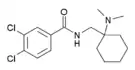

The pharmacodynamic response to an opioid depends upon the receptor to which it binds, its affinity for that receptor, and whether the opioid is an agonist or an antagonist. For example, the supraspinal analgesic properties of the opioid agonist morphine are mediated by activation of the μ1 receptor; respiratory depression and physical dependence by the μ2 receptor; and sedation and spinal analgesia by the κ receptor. Each group of opioid receptors elicits a distinct set of neurological responses, with the receptor subtypes (such as μ1 and μ2 for example) providing even more [measurably] specific responses. Unique to each opioid is its distinct binding affinity to the various classes of opioid receptors (e.g. the μ, κ, and δ opioid receptors are activated at different magnitudes according to the specific receptor binding affinities of the opioid). For example, the opiate alkaloid morphine exhibits high-affinity binding to the μ-opioid receptor, while ketazocine exhibits high affinity to ĸ receptors. It is this combinatorial mechanism that allows for such a wide class of opioids and molecular designs to exist, each with its own unique effect profile. Their individual molecular structure is also responsible for their different duration of action, whereby metabolic breakdown (such as N-dealkylation) is responsible for opioid metabolism.

A new strategy of drug development takes receptor signal transduction into consideration. This strategy strives to increase the activation of desirable signalling pathways while reducing the impact on undesirable pathways. This differential strategy has been given several names, including functional selectivity and biased agonism. The first opioid that was intentionally designed as a biased agonist and placed into clinical evaluation is the drug oliceridine. It displays analgesic activity and reduced adverse effects.[162]